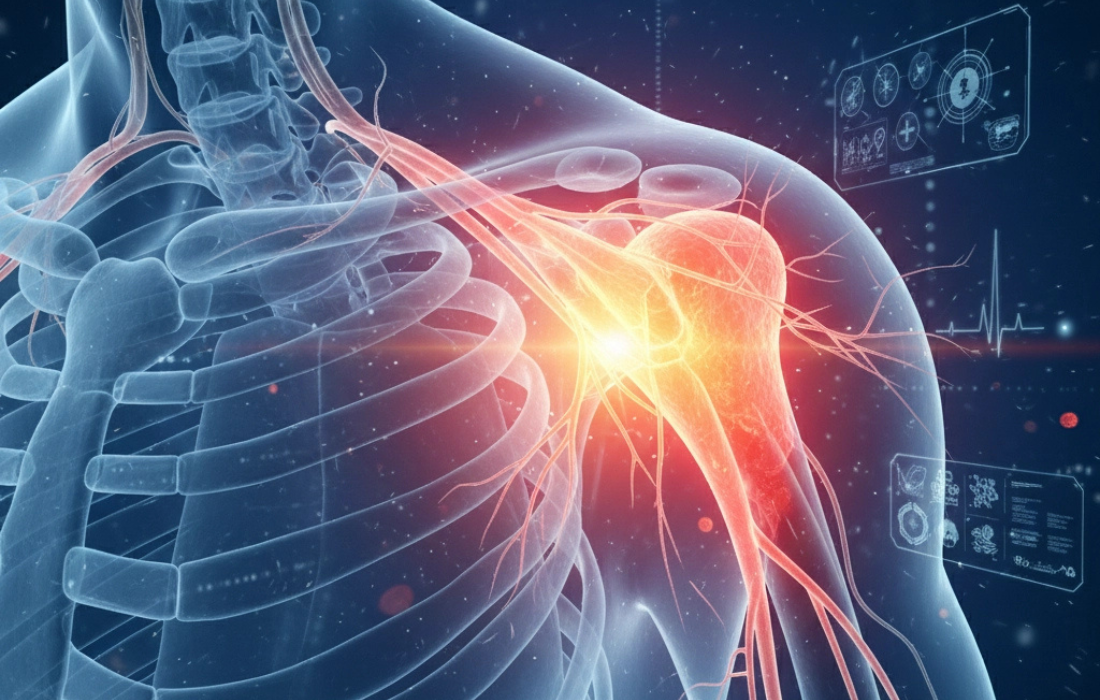

¿QUÉ ES LA BURSITIS DE HOMBRO Y POR QUÉ DUELE TANTO?

Con regularidad, los pacientes que se quejan de dolor en el hombro al levantar el brazo, cargar objetos o dormir sobre un lado son atendidos en nuestro consultorio.